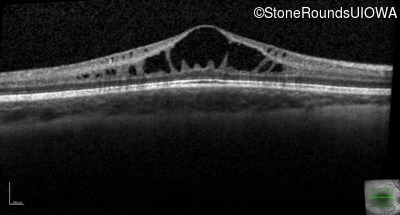

XL Retinoschisis (IIIB1)

XL Retinoschisis (IIIB1)

This 6 year old boy first experienced difficulty reading and seeing the blackboard at age 5.

| XL Retinoschisis | RS1 | Pro192His CCC>CAC | XL |